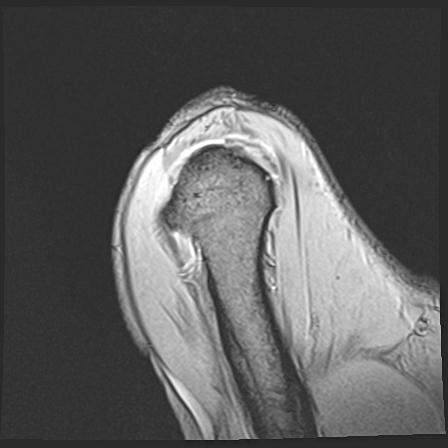

60058 3/9 11/4 右肩 2R+MRI 73歳男性 肩腱板損傷